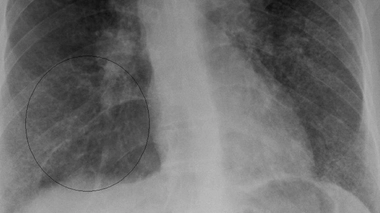

La sarcoïdose, la maladie des granulomes

Radiographie du thorax d'une personne atteinte de sarcoïdose, la zone cerclée présente une accumation de granulomes. (cc-by-sa Jmh649)